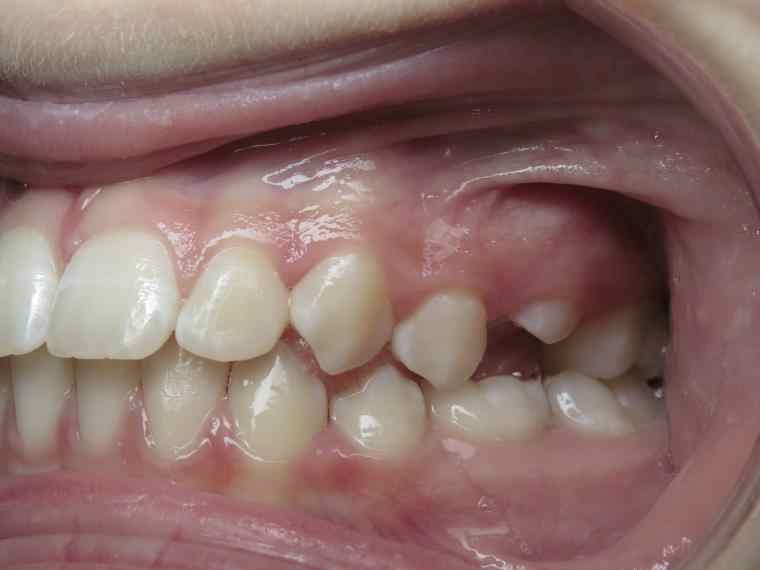

inversion postérieur coté droit et espace entre les dents du haut et du bas (diastèmes)

appareillage mobile pendant 35 mois

surveillance évolution de la dentition pendant 5 ans